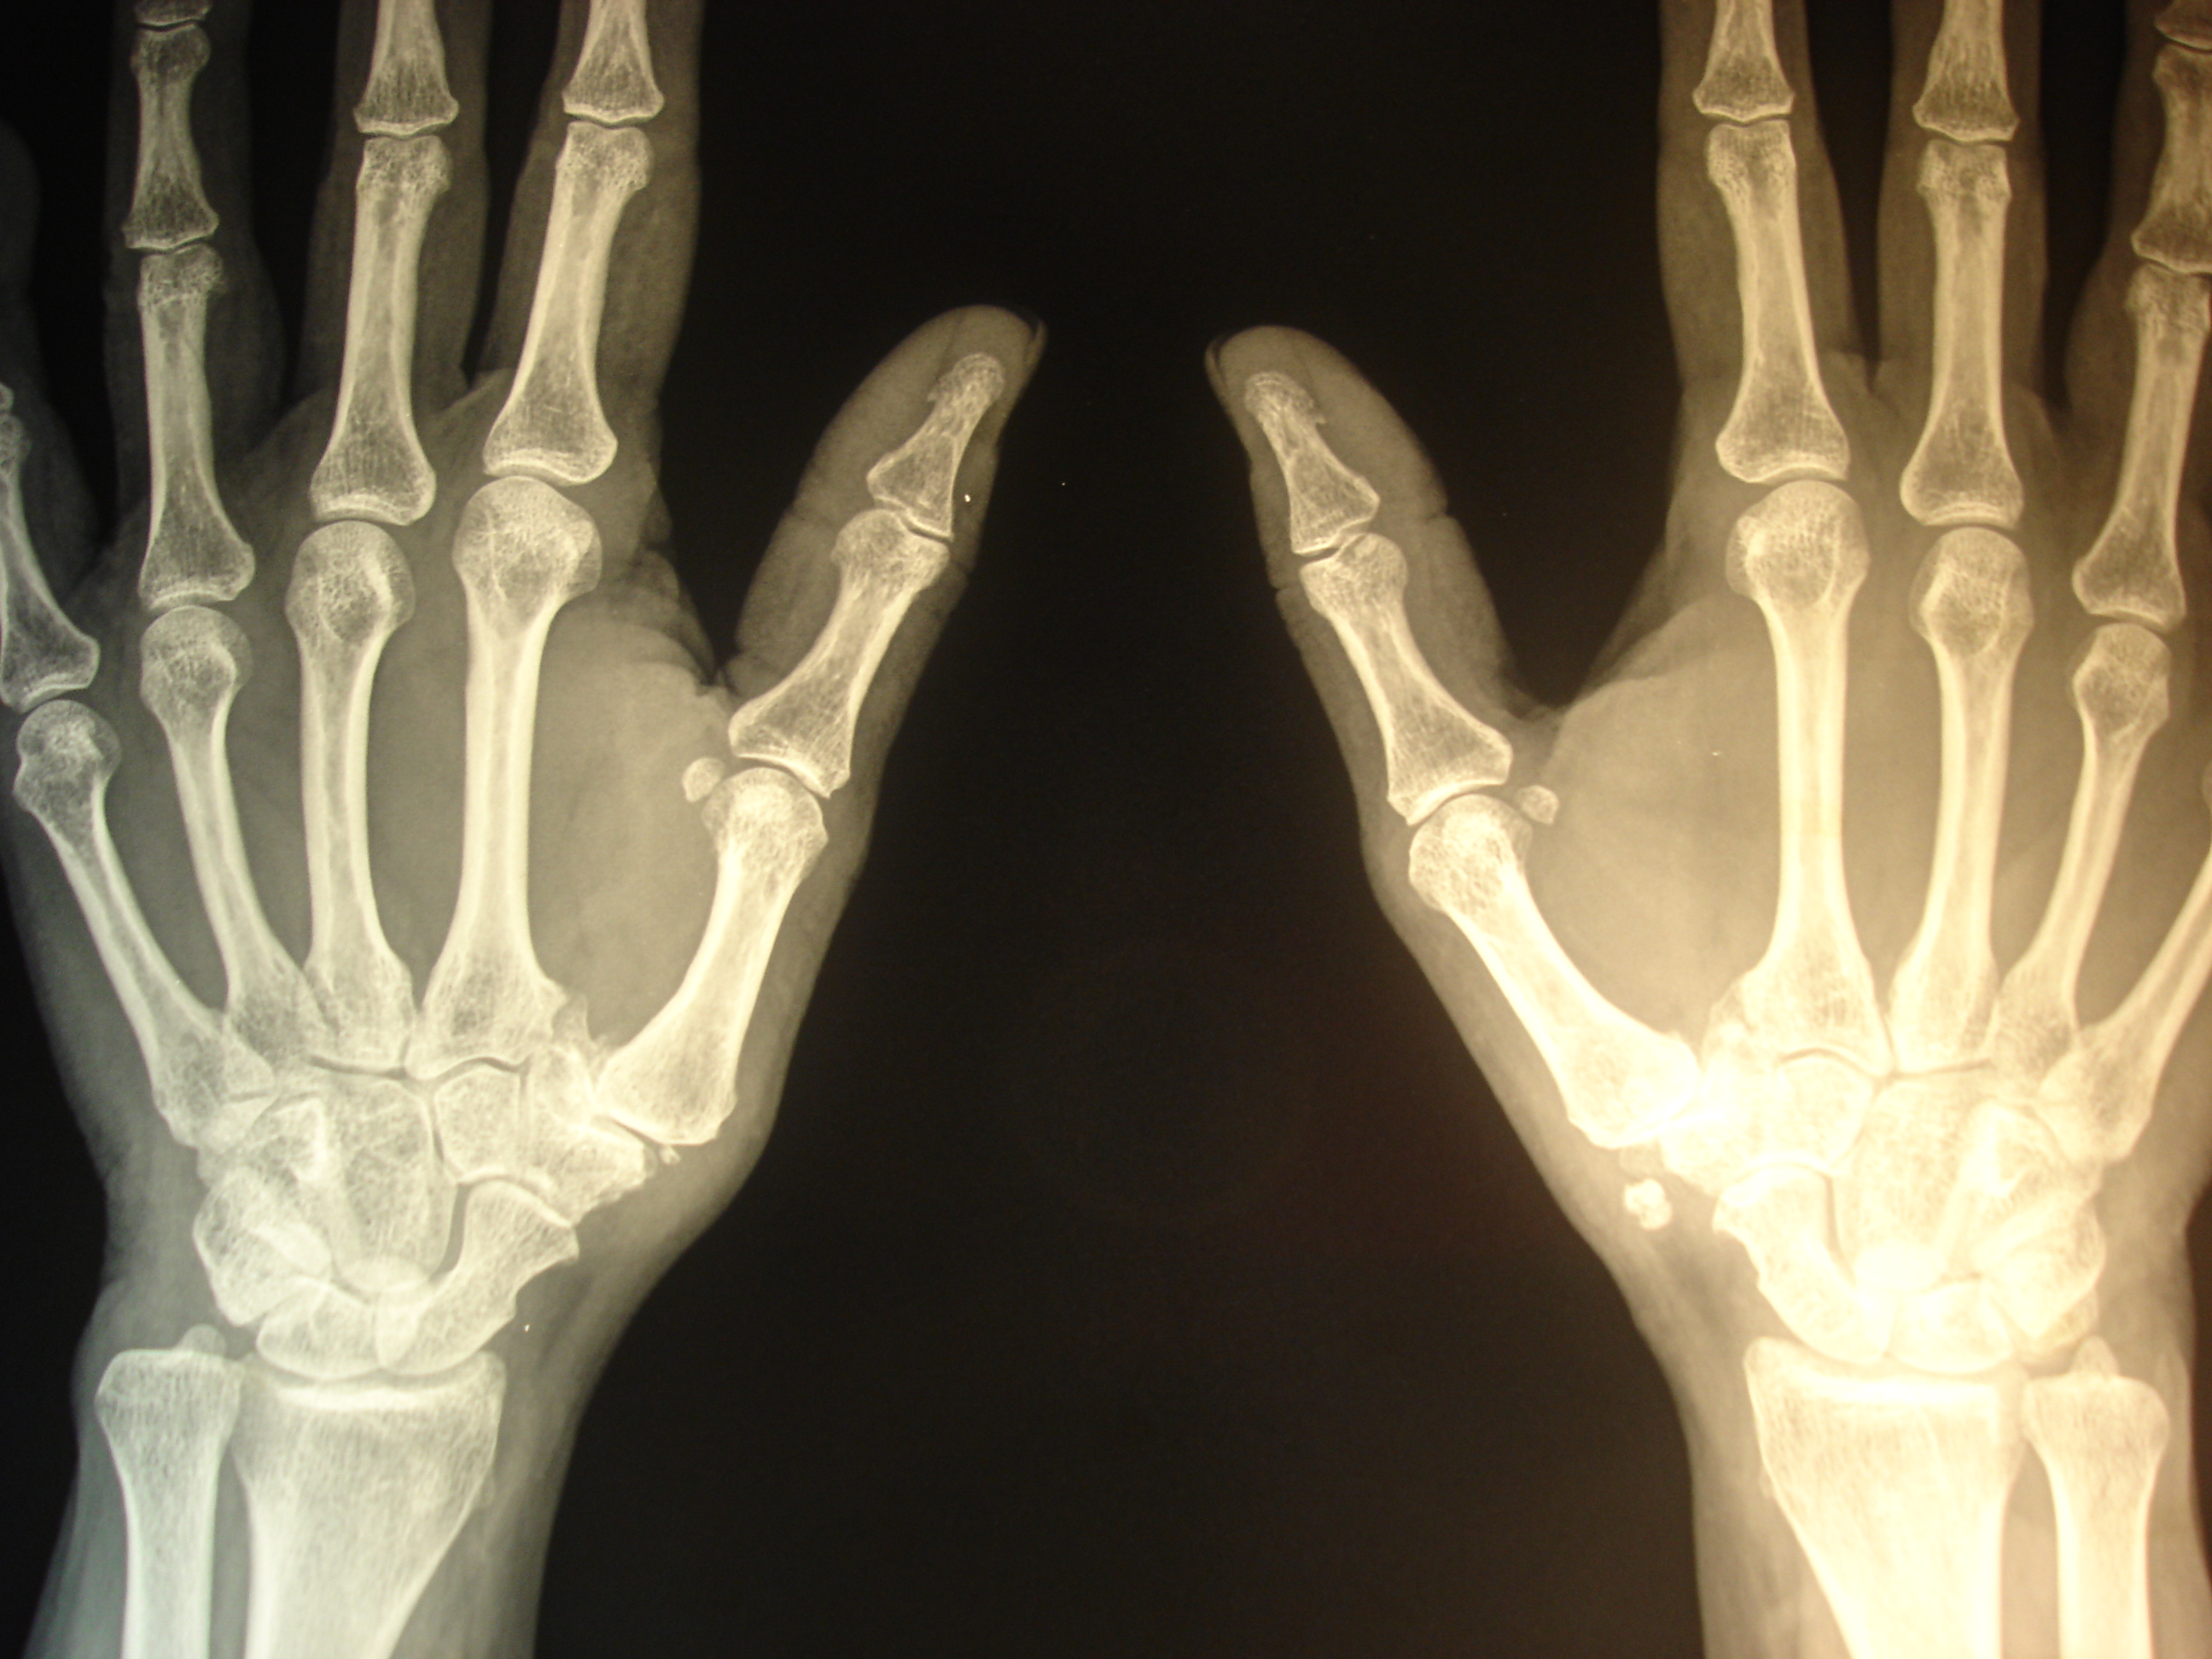

Uno de los procesos que mejor evolucionan tras la colocación de implantes de oro periarticulares es la rizartrosis del pulgar. Puede que al no ser una articulación de carga la respuesta al tratamiento sea más rápida. La degeneración articular con la pérdida de la congruencia anatómica no es un obstáculo para la recuperación funcional; la mejoría de la movilidad y la fuerza de prensión digital son notables en los casos tratados, así como la disminución-supresión del dolor. Parece cada día más evidente el relevante papel de los tejidos blandos articulares y periarticulares en la morbilidad  articular. Uno de los efectos biomédicos descritos en experimentación animal es la competencia local del oro con el calcio que se observa en las exóstosis y calcificaciones periarticulares. Se aprecia en las siguientes RX el caso de una paciente con rizartrosis de pulgar bilateral que requería una ingesta diaria de diclofenaco durante 12 años, que suspendió al día siguiente de la intervención hace unos 4 meses. Puede verse un cambio significativo en la calcificación de la mano izquierda. Es uno de los casos (bilateral) en el que el resultado funcional (movilidad y fuerza).

era muy satisfactorio para la paciente (aunque en la mano derecha era muy bueno pero persistía algo de dolor). Luego de 4 meses, en el momento de colocar implantes en las rodillas se colocó un implante más en la cara palmar de la articulación metacarpofalángica que era algo sintomática. Se puede ver en la RX interaoperatoria. El resultado inmediato ha sido muy satisfactorio.

aparente disminución de la calcificación en la mano izquierda